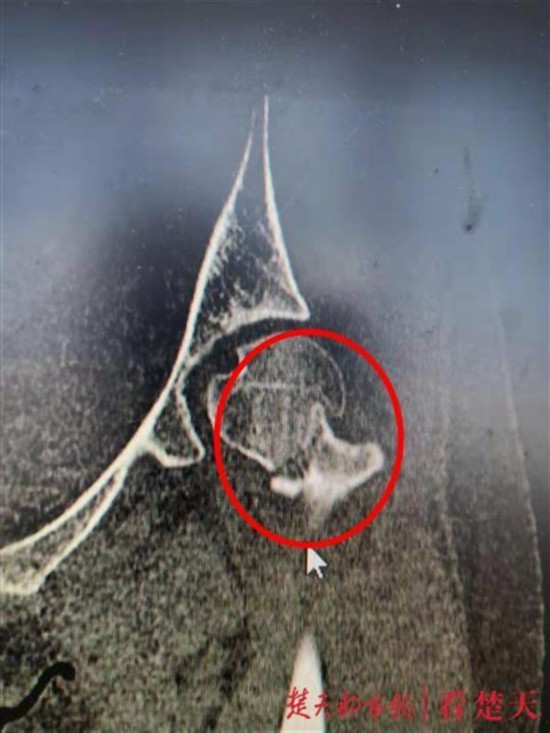

据接诊医生介绍,刘女士从高处摔下后,全身重量集中在了左侧,压断了股骨颈,磁共振片清楚地显示,她的左侧股骨颈粉碎性骨折,需进行手术固定,防止股骨头坏死和骨折不愈合。21日上午,在骨科机器人辅助下,医生们用三枚螺钉将刘女士骨折处固定后,顺利完成了手术。